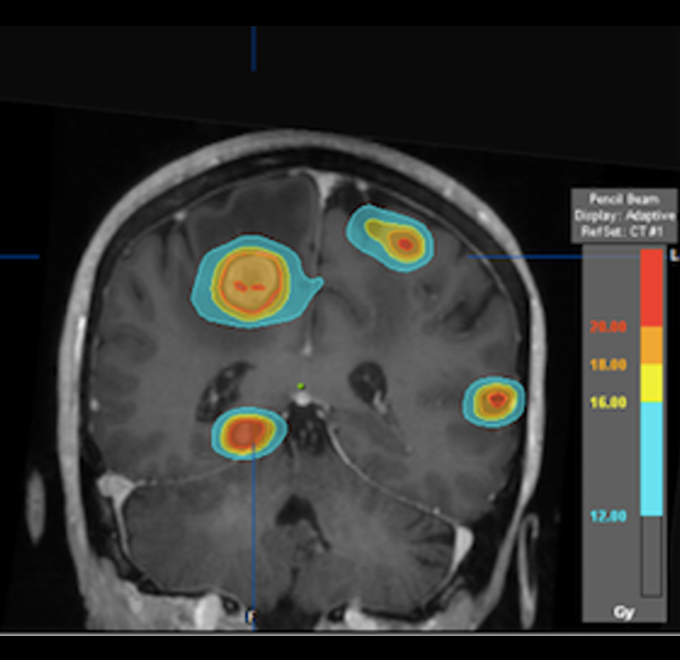

El Centro Médico Saludora ha recibido la certificación de la International Society for Stereotactic Radiosurgery (ISRS), un reconocimiento que resalta nuestro compromiso con la excelencia en el tratamiento de pacientes mediante radiocirugía estereotáctica intracraneal (SRS). Esta certificación nos coloca como el único hospital en México y uno de los cuatro centros de salud en América Latina especializados en el uso de estas tecnologías avanzadas, mediante aceleradores lineales de electrones (8 NOVALIS TX), que ofrecen una precisión submilimétrica, similar al Gamma Knife con la ventaja de realizar una sesión de tratamiento más rápida (aproximadamente 60-90 minutos, en lugar de las 2-3 horas requeridas por otros dispositivos).

Contamos con más de 10 años de experiencia en el uso de estas tecnologías, brindando tratamientos altamente precisos para tumores cerebrales, patologías benignas y patologías funcionales. Con esta certificación, nuestros pacientes pueden confiar en que recibirán atención médica de la más alta calidad, respaldada por un equipo multidisciplinario compuesto por radio-oncólogos, neurocirujanos acreditados para radiocirugía, oncólogos médicos, físicos médicos, entre otros profesionales altamente capacitados.

Además, todos los casos tratados son revisados mediante un proceso de revisión por pares (peer review), esto permite que las indicaciones clínicas y planificaciones sean evaluadas en un tumor board antes de iniciar el tratamiento. Utilizamos imágenes de resonancia magnética de alta calidad para asegurar que cada detalle sea considerado en el plan de tratamiento, lo que respalda nuestra precisión y cuidado.

La Radiocirugía Estereotáctica (SRS) es un tratamiento avanzado y preciso utilizado para tratar lesiones intracraneales, realizado por un equipo multidisciplinario que incluye un radio-oncólogo y un neurocirujano acreditado en radiocirugía. Esta técnica permite aplicar radiación de alta precisión directamente sobre el tumor en el cerebro, minimizando el impacto en los tejidos sanos circundantes.

Metástasis Cerebrales (MTX SNC): Las metástasis cerebrales son tumores que se originan en otro órgano, como el pulmón, mama o próstata, y se propagan al cerebro. La radiocirugía permite tratarlas con precisión, ayudando a reducir su tamaño o detener su crecimiento sin necesidad de cirugía invasiva.

Tenemos experiencia en el tratamiento de oligometastasis (enfermedad metastásica pequeña en número y tamaño), en la cual el tratamiento muy selectivo y preciso con radiocirugía ha demostrado beneficio, además de poderse tratar varias lesiones a la vez.